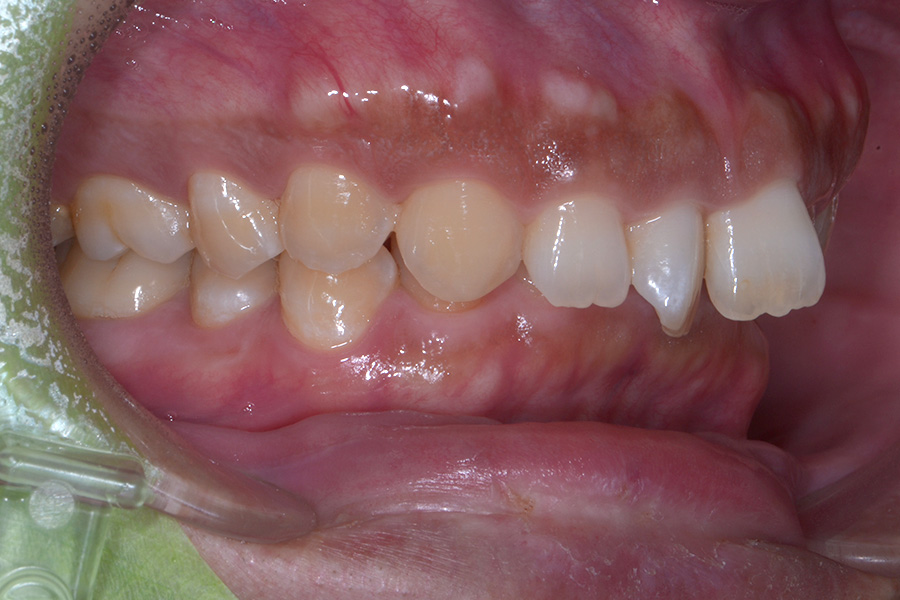

治療後

主訴 捻じれている歯を引っ込めたい

期間 8か月

費用 治療費35万円(別途調整料)

治療内容 上顎リンガル矯正(裏側矯正)